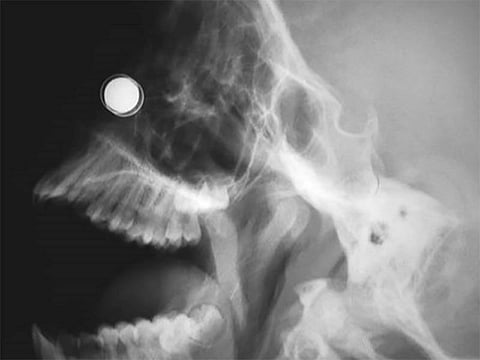

X-ray of embedded magnet in a pediatric patient Image: NEJM 2017

The aim is to reduce injuries that can occur when swallowed magnets attract to each other inside the body. The risks include perforations, twisting and/or blockage of the intestines, infection, blood poisoning and even death.

Injuries can occur when kids ingest magnets, for example to mimic mouth piercings.